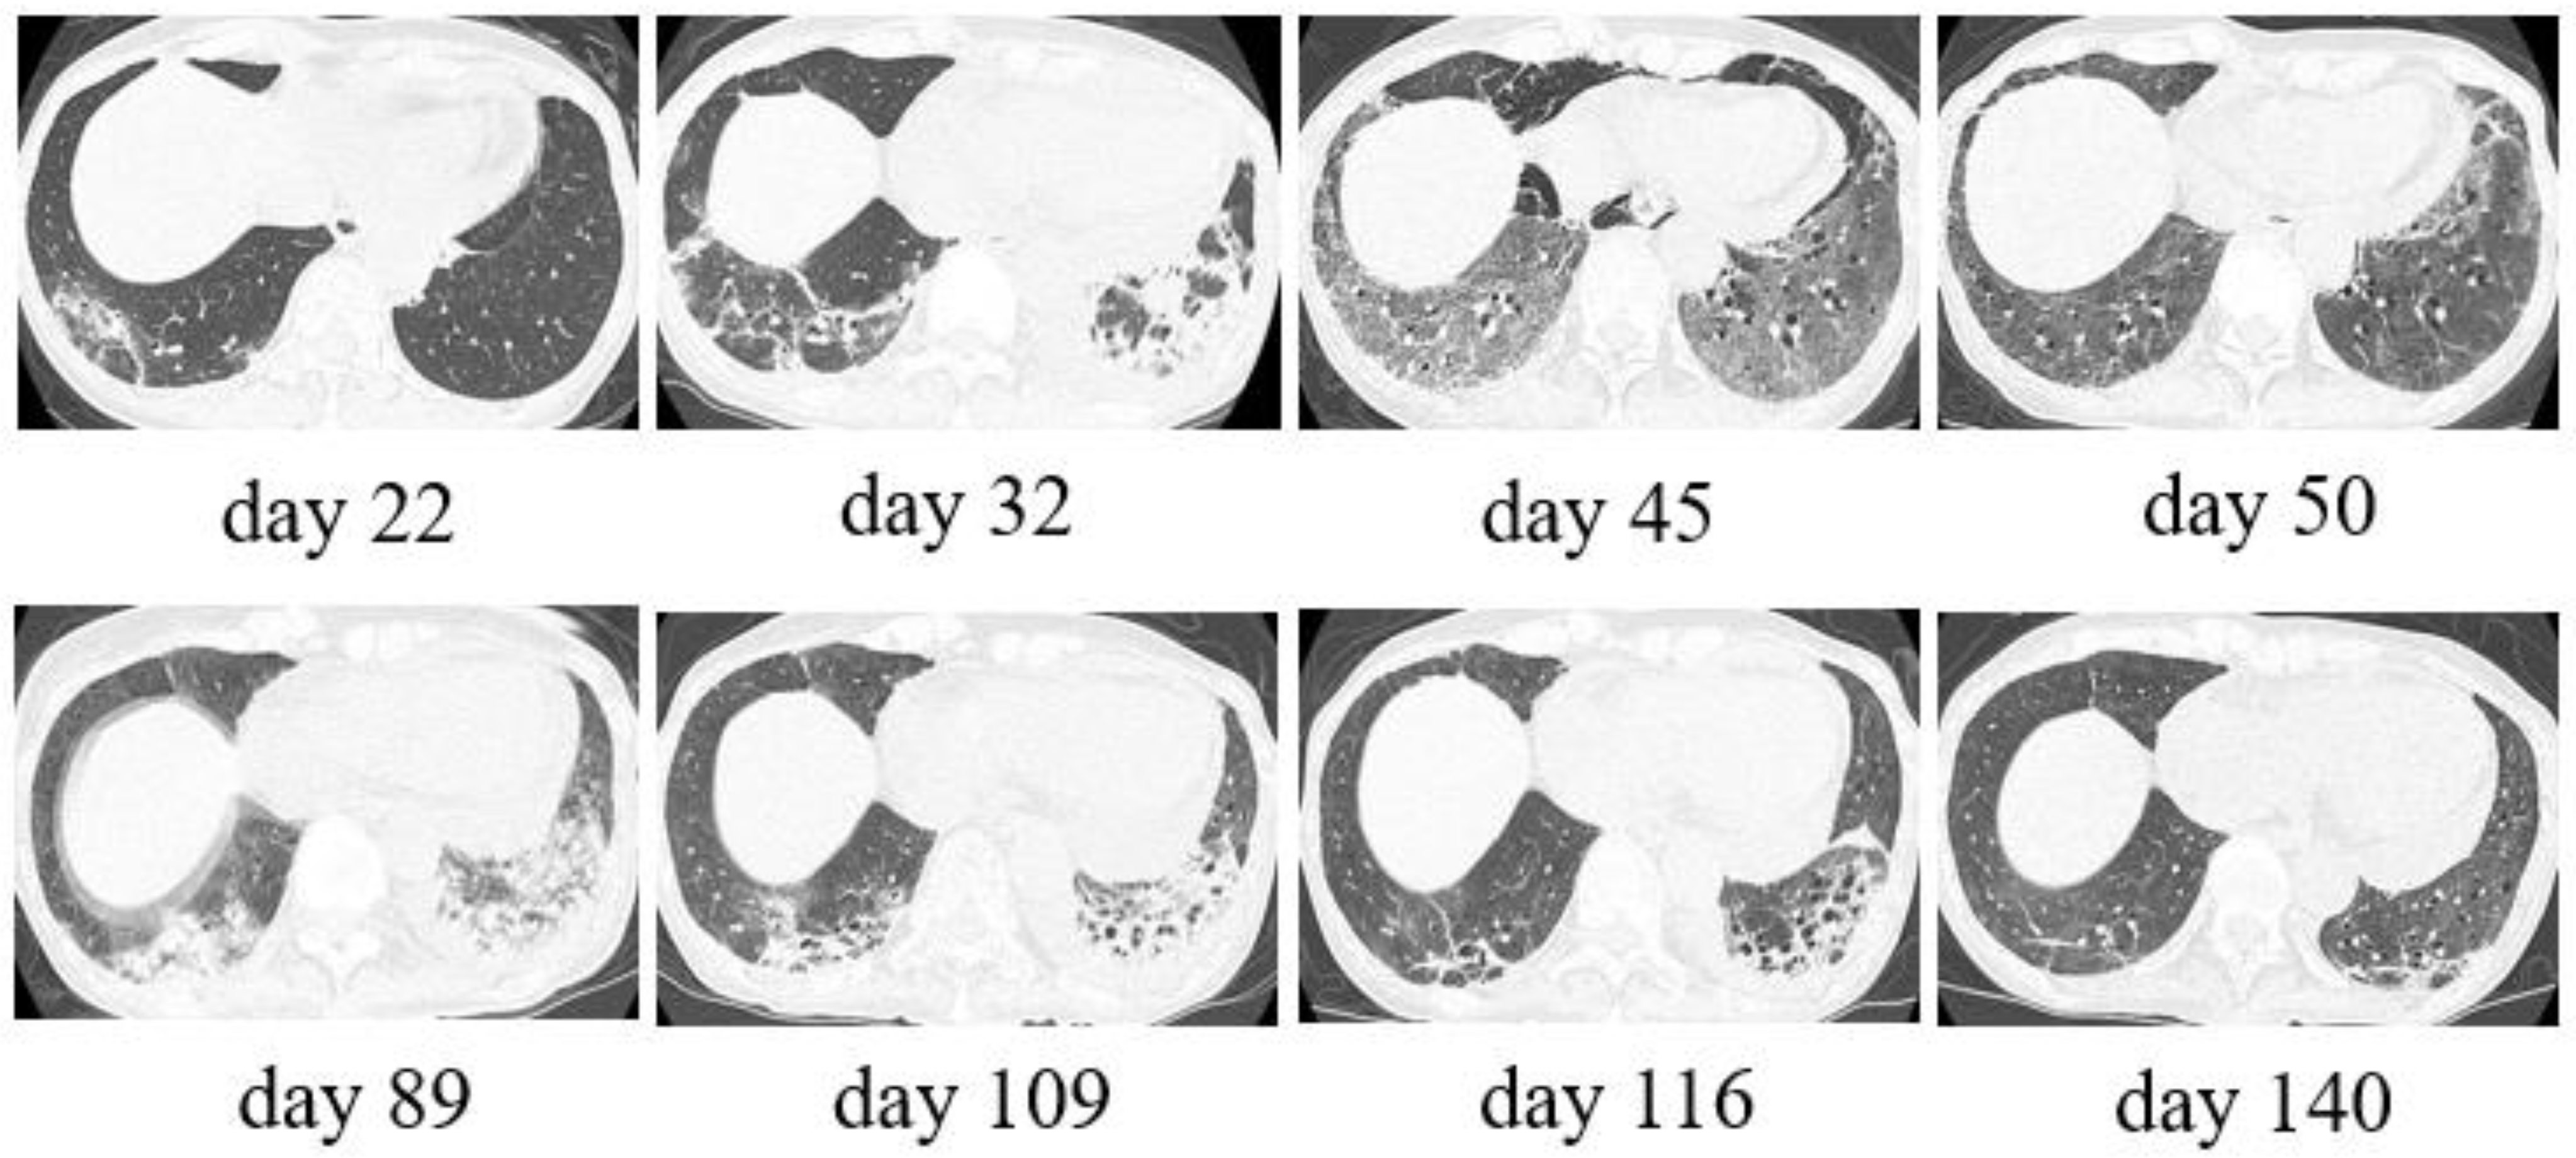

3. Case